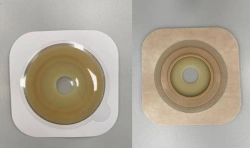

Medical product is intended for use in colostomies, ileostomies and urostomies for hermetic and secure attachment of stoma bags to the skin of the anterior abdominal wall, as well as to protect the skin of the peristomal area from stoma secretions and preserve the physiological functions of the skin due to the absorption of natural skin moisture (sweat, sebum).